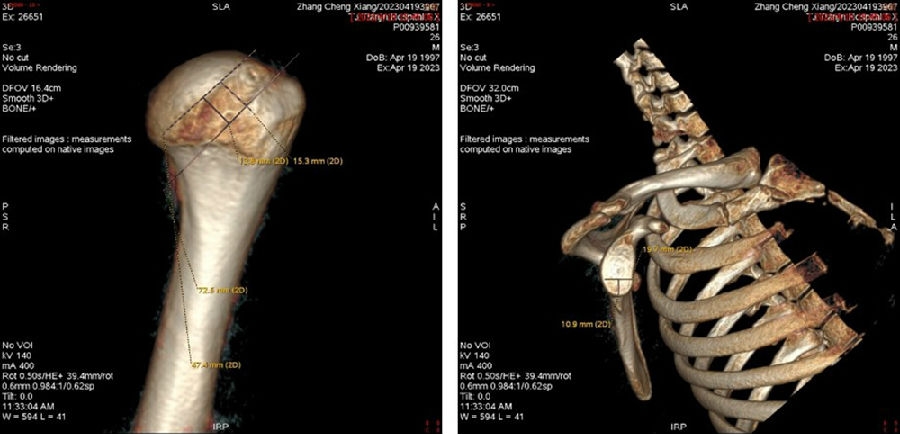

双侧CT三维扫描显示:健侧肩胛盂宽度D=25.9,患侧D=23.9,患侧肩胛盂骨性缺损d=6.2,骨性盂唇缺损面积d/D为23.9%(<25%)。肩胛盂轨迹GT(83%D-d)为15.3mm。

图28双侧CT三维扫描

图29 Hill-Sachs间隙为13.8mm(<15.3mm)

图30 评估结果

评估报告提示:右肩胛骨关节盂前下缘撕脱骨折,符合骨性bankart损伤。右肱骨头后上缘凹陷骨折,符合Hill-Sachs损伤。Hill-Sachs间隙为13.8mm(<15.3mm),为轨迹内肩关节前脱位。